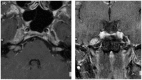

Intracranial trigeminal schwannomas are rare tumors. Patients usually present with symptoms of trigeminal nerve dysfunction, the most common symptom being facial pain. MRI is the imaging modality of choice and is usually diagnostic in the appropriate clinical setting. The thin T2-weighted CISS 3D axial sequence is important for proper assessment of the cisternal segment of the nerve. They are usually hypointense on T1, hyperintense on T2 with avid enhancement post gadolinium. CT scan is supplementary to MRI, particularly for tumors located in the skull base. Imaging plays a role in diagnosis and surgical planning. In this pictorial essay, we retrospectively reviewed imaging findings in nine patients with pathologically proven trigeminal schwannoma. Familiarity with the imaging findings of intracranial trigeminal schwannoma may help to diagnose this entity.